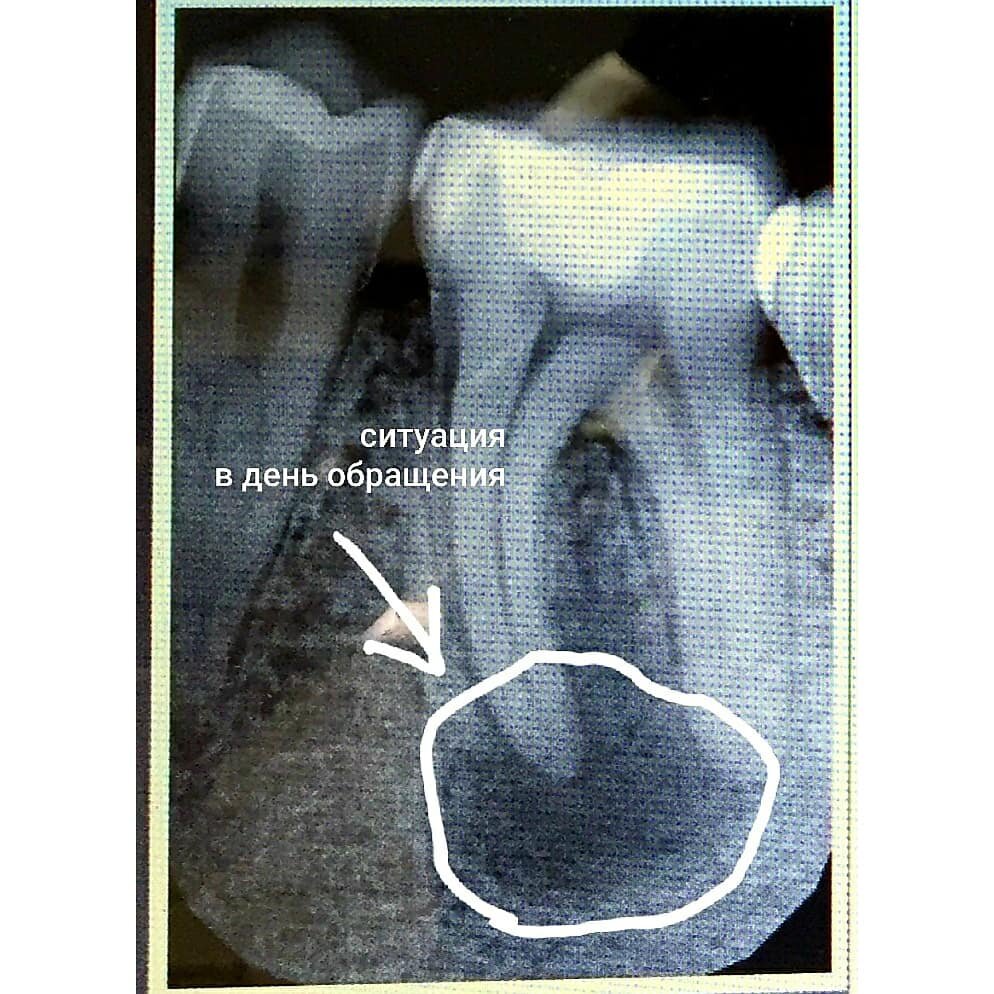

Ситуация в день обращения, на фото обведен очаг воспаления вокруг корня зуба